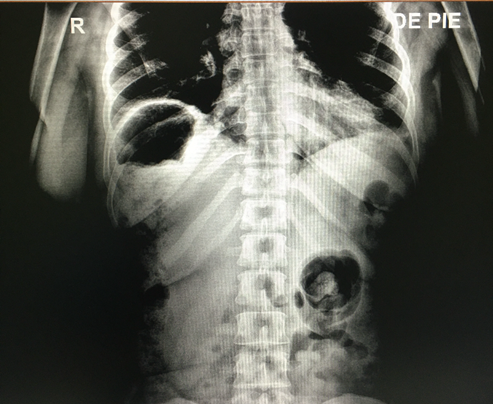

Se realizo una radiografía abdominal que revela la presencia de pseudoneumoperitoneo (Fig.1). Posteriormente, una tomografía computarizada abdominal evidencia colon derecho sobre la superficie hepática (Fig.2).

Su diagnóstico requiere estudios de imagen que confirmen la anomalía, cumpliendo los siguientes tres criterios:

El hemidiafragma derecho debe estar elevado por el intestino.

Debe simular un neumoperitoneo.

El borde superior del hígado debe encontrarse por debajo del diafragma izquierdo, tal como se evidenció en el caso presentado.2